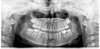

Traitement Invisalign débuté chez une jeune patiente de 7 ans qui présentait une agénésie de la 35 (absence du germe d’un prémolaire définitive) et un encombrement important : les incisives latérales supérieures n’avaient pas de place pour évoluer. Compte du jeune de la patiente et de son sérieux, il a été choisi de ne pas extraire, mais de faire de l’expansion et d’avancer la molaire mandibulaire à la place de la prémolaire absente, afin de permettre à la jeune patiente de ne pas avoir d’implant à l’âge adulte. Le traitement a été réalisé en plusieurs étapes, s’adaptant à l’évolution des dents définitives. Voici quelques-unes de ces étapes.